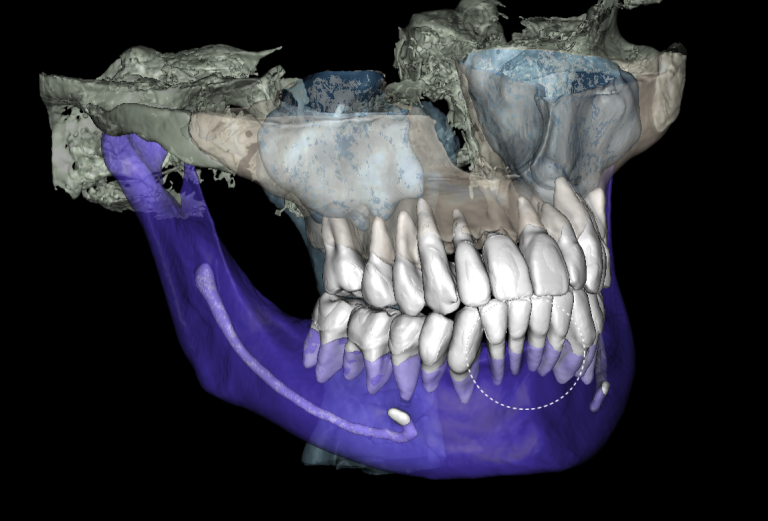

Fully automatic segmentation and creation of 3D models from DICOM files allows you to select individual structures for printing models on a 3D printer

Based on these models, stereolithographic models were produced to plan the placement of the titanium mesh and ensure its accurate fit